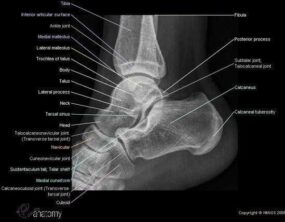

Las radiografías, generalmente llamadas rayos X, producen imágenes como sombras de huesos y ciertos órganos y tejidos. Las radiografías son muy buenas para detectar problemas óseos. Pueden mostrar algunos órganos y tejidos blandos; sin embargo, la MRI y la CT suelen crear mejores imágenes de los mismos. Aun así, las radiografías son rápidas, fáciles de obtener y menos costosas que los otros estudios, por lo que se pueden usar para obtener información rápidamente.

Un tubo especial dentro de la máquina de rayos X emite un haz de radiación controlada. Los tejidos del cuerpo absorben o bloquean la radiación en diferentes grados. Los tejidos densos como los huesos bloquean la mayor parte de la radiación, pero los tejidos blandos, como la grasa o los músculos, bloquean menos radiación. Después de pasar por el cuerpo, el haz alcanza una pieza de un fragmento de película o un detector especial. Los tejidos que bloquean altas cantidades de radiación, como los huesos, aparecen como áreas blancas en un fondo negro. Los tejidos blandos bloquean menos radiación y aparecen en tonos de gris. Los órganos que contienen principalmente aire (como los pulmones) aparecen en negro. Los tumores son por lo general más densos que el tejido que los rodea, por lo que suelen verse en tonos grises más claros.